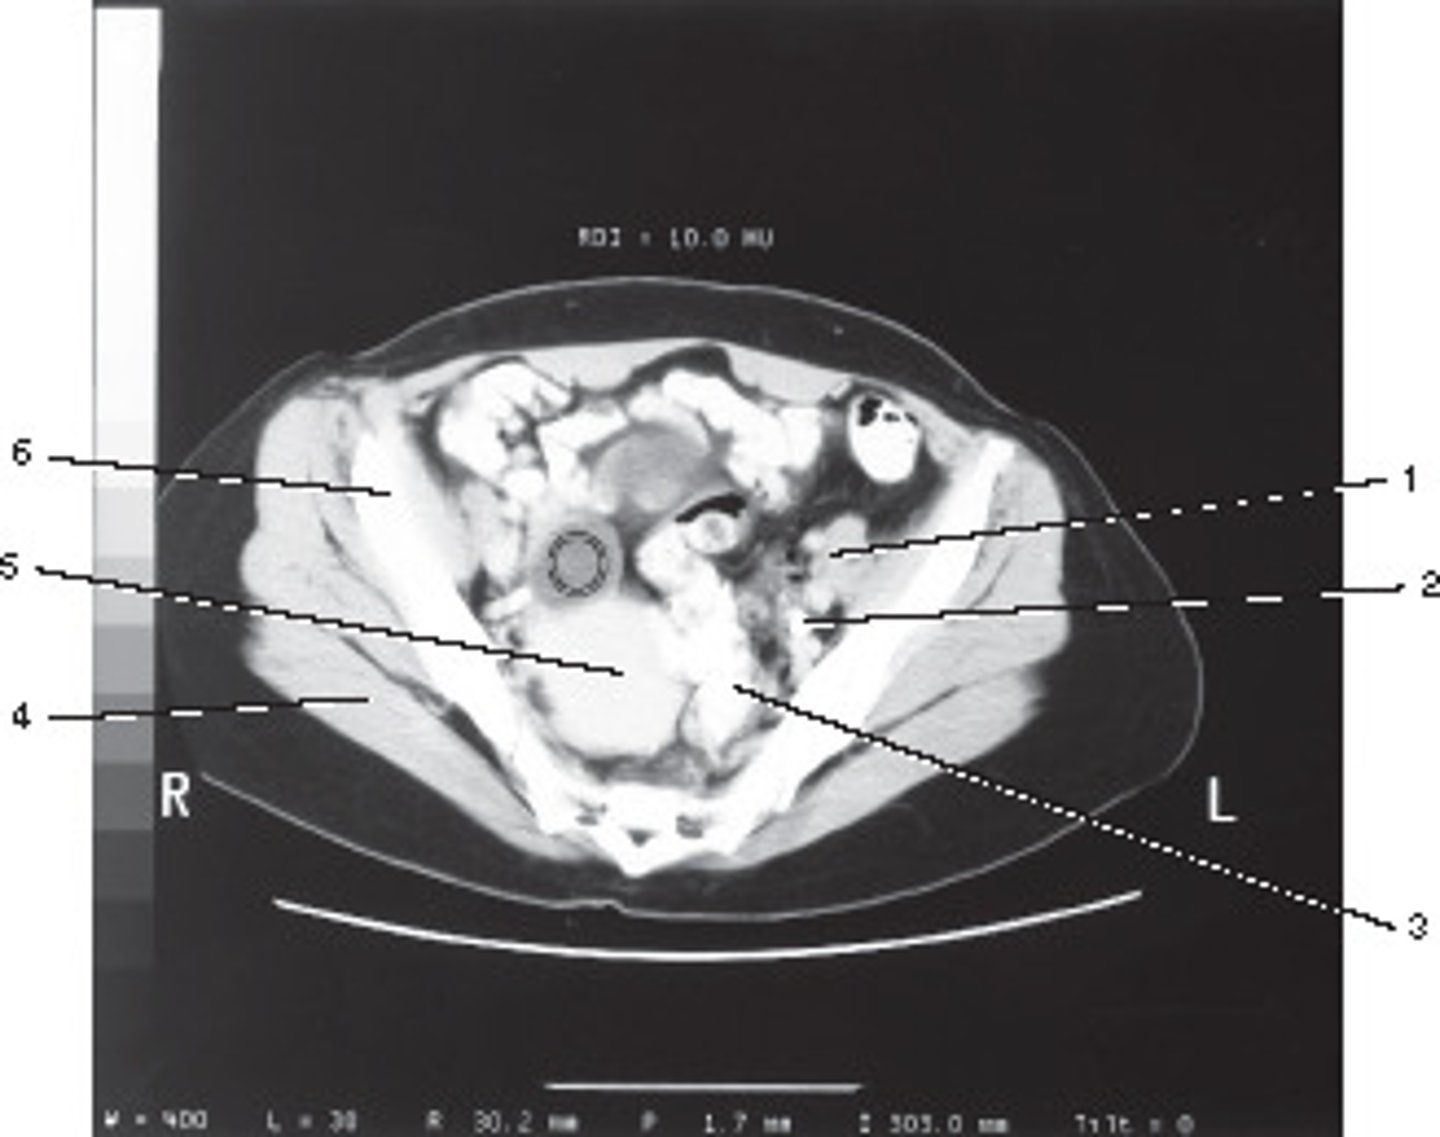

Ovarian Cyst

This ROI has a HU value of +10, given its position in a female bony pelvis, this most likely represents:

<p>This ROI has a HU value of +10, given its position in a female bony pelvis, this most likely represents:</p>

Inferior Vena Cava

Number 8 corresponds to which of the following?

<p>Number 8 corresponds to which of the following?</p>

Number 4 corresponds to which of the following?

<p>Number 4 corresponds to which of the following?</p>

Number 6 corresponds to which of the following?

<p>Number 6 corresponds to which of the following?</p>